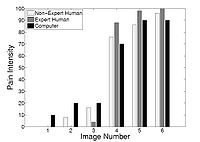

Agitation and Pain Assessment Using Digital ImagingPain assessment in patients who are unable to verbally communicate with medical staff is a challenging problem in patient critical care. The fundamental limitations in sedation and pain assessment in the intensive care unit (ICU) stem from subjective assessment criteria, rather than quantifiable, measurable data for ICU sedation and analgesia. This often results in poor quality and inconsistent treatment of patient agitation and pain from nurse to nurse. Recent advancements in pattern recognition techniques using a relevance vector machine algorithm can assist medical staff in assessing sedation and pain by constantly monitoring the patient and providing the clinician with quantifiable data for ICU sedation. In this paper, we show that the pain intensity assessment given by a computer classifier has a strong correlation with the pain intensity assessed by expert and non-expert human examiners.More... New: B. Gholami, W. M. Haddad, and A. Tannenbaum, Relevance Vector Machine Learning for Neonate Pain Intensity Assessment Using Digital Imaging. IEEE Trans. Biomed. Eng., vol. 57, pp. 1457-1466, 2012. New: B. Gholami, W. M. Haddad, and A. R. Tannenbaum, Agitation and Pain Assessment Using Digital Imaging. Proc. IEEE Eng. Med. Biolog. Conf., Minneapolis, MN, pp. 2176-2179, 2009 (Awarded National Institute of Biomedical Imaging and Bioengineering/National Institute of Health Student Travel Fellowship). New: Wassim M. Haddad, James M. Bailey, Behnood Gholami, and Allen Tannenbaum. Optimal Drug Dosing Control for Intensive Care Unit Sedation Using a Hybrid Deterministic-Stochastic Pharmacokinetic and Pharmacodynamic Model. Optimal Control, Applications and Methods}, 2012, DOI: 10.1002/oca.2038. |